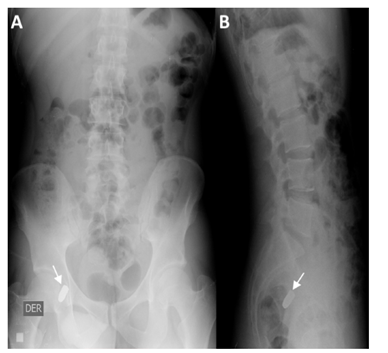

A 31-year-old man with no previous medical history was taken to the emergency department after suffering multiple injuries from a firearm, a chest wound and two in the right upper extremity, at a distance of approximately 8 meters, the gun caliber is unknown. The patient was alert, oriented with Glasgow 15/15 coma scale, normal vital signs, central and peripheral pulses, strong and symmetric, hemodynamically stable and negative shock index. The physical examination showed wounds with an entrance and exit hole in the proximal third of the right upper limb, another entrance and exit hole at the level of the hand of the same extremity. An entrance orifice was identified in the right deltoid region, without exit orifice. No wound had hard or soft signs of vascular injury. The initial chest radiograph shows a projectile in the right cervicothoracic region, without other findings (Figure 1). At six o'clock a new chest X-ray is performed, in which the projectile is not observed in the initial position (Figure 2). Radiography of the neck is performed, where the absence of the projectile is verified in the cervicothoracic space (Figure 3), but the abdomen radiograph shows the projectile in the right iliac fossa Figure 4(A,B). The follow-up with computed tomography without and with contrast of abdomen and pelvis showed the projectile lodged in right internal iliac vein (Figure 5). A grayscale and Doppler ultrasound study of the neck showed a small hematoma in place where the projectile was initially lodged without clearly demonstrating the path of communication with the right jugular vein by ultrasound. Because the patient was asymptomatic, the decision was made to treat the patient conservatively. After 2 years of follow-up, the patient remains asymptomatic.

Figure 4(A) Radiography of abdomen in frontal (A) and lateral (B) projection in which projectile is visualized, housed in topography of the right internal iliac fossa.